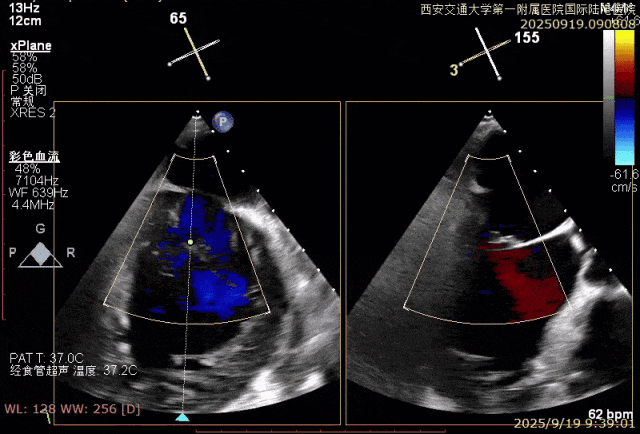

患者男性,69岁,术前TEE评估为FMR患者,因左室功能异常引发二尖瓣重度反流;后叶拴系,反流来源于整个2区,主要集中在2偏1、2偏3。患者瓣口面积约6.2cm²。房间隔可穿刺高度4.5cm。反流束宽度约19mm。AP径36.5mm。

术中在超声引导下完成房间隔穿刺,将第一枚XTR在左房内完成终定位,2偏3区完成植入,夹合效果良好,即刻超声显示轻微反流,完成夹子释放,手术效果良好,手术圆满结束,患者术后6小时即实现床旁活动。